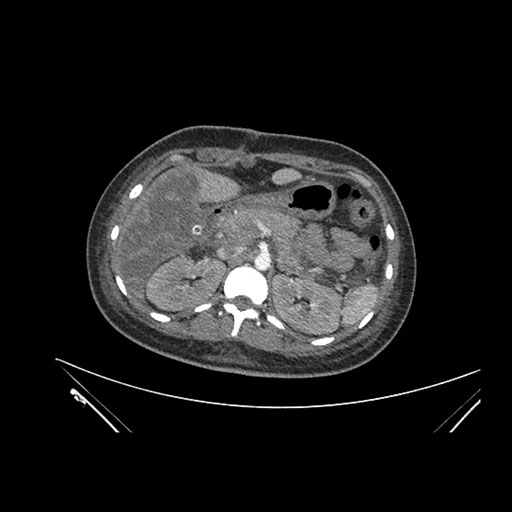

Axial Arterial

Imaging analysis

Based on initial findings, which issue(s) would you be most concerned about?